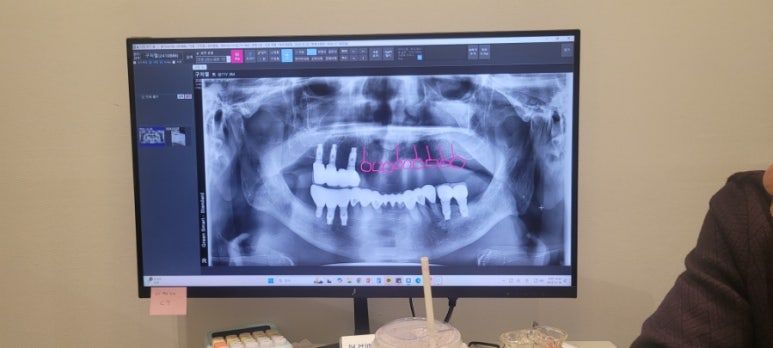

아빠는 현재 윗니는 틀니로 생활하고 계셨다.

잇몸 건강이 노화되면서 임플란트 식립했던게 지탱하기 힘들었던 상황이다.

1.jpg

이번 치료를 통해 윗니 9개를 브릿지 하신다

6개는 식립하고 3개는 걸어서 사용하신다고 한다.

아빠는 이전 임플란트 치료시 국가 보조금 2개를 이미 사용하셔서 나라 지원금 없이 결제 하셔 총 300만원 견적이 나왔다.

선금 20만원

식립시 130만원

상학동거상술시 80만원

본뜨기시 70만원